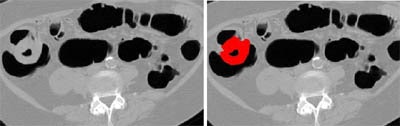

![]() |

| Large circumferential mass in the cecum (far left). Red area (right image) indicates the mass region extracted by the CAD scheme for the detection of masses. Images courtesy of Dr. Hiro Yoshida. |